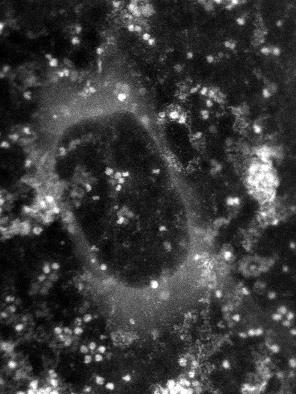

In this image generated by an electron microscope, the white dots are the protein ferritin. The dark circle in the middle is a bubble trapped within the graphene capsule enclosing the sample, proving the existence of a liquid.

“Graphene is just a single layer of carbon atoms, and electrons can go through it easily, but water does not,” Klie said. “If you put a drop of water on graphene and top it with graphene, it forms this little balloon of water.” The graphene is strong enough to hold the water inside, even within the vacuum of an electron microscope.

The team made a microscopic sandwich, with ferritin immersed in water as the filling and graphene as the bread, and sealed the edges. Then, using a scanning transmission electron microscope, they captured a variety of images showing ferritin’s atomic structure. In addition, they used a special type of spectroscopy to identify various atomic and electronic structures within the ferritin. Those images showed that the ferritin was releasing iron and pinpointed its specific form.